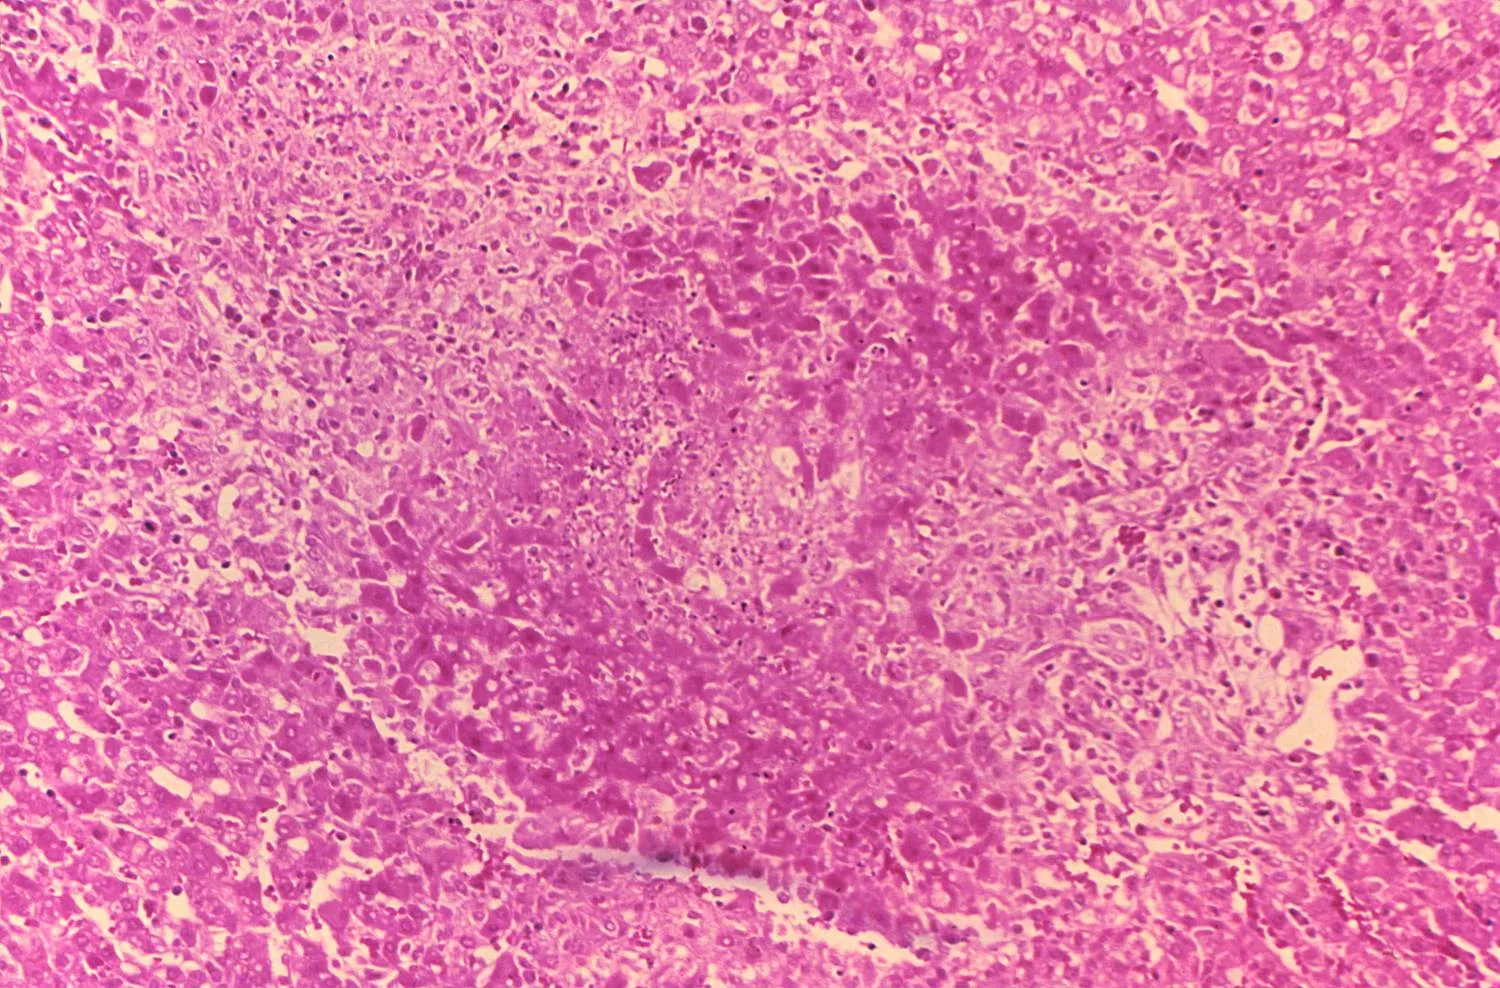

A krónikus formában évekig fennállhatnak a pananaszok, hosszabb tünetszegény, láztalan, illetve hőemelkedéstől mentes periódusokkal tarkítva. A férfiak mellékheréjét az esetek alig több mint tizedében támadják meg a brucellák. A betegekben megnagyobbodhatnak a nyirokcsomók, a lép, ritkábban a máj is.

Prognózisa kezelés nélkül rossz, az elhúzódó betegség csont- és ízületi károsodásokhoz vezet. Súlyos szövődmény az endokarditisz (szívbelhártya-gyulladás, a szívizomra többnyire nem terjed), a szívbillentyűk károsodása. Előfordulhat továbbá hepatitisz, epehólyag-gyulladás, pneumonitisz (intersticiális, azaz a tüdő légcserében részt nem vevő szöveteinek gyulladása mellhártya izzadmánnyal).